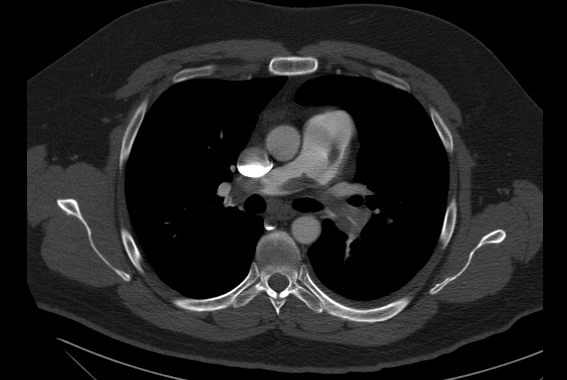

A 47 year-old male with no medical history presented with dyspnea and pleuritic chest pain to a local ER. His blood pressure was 135/60, heart rate was 108 bpm, and his oxygen saturation was 94% on 2L oxygen per nasal cannula. He has recently been on a 12 hour transatlantic flight for business. A CT showed bilateral main pulmonary artery embolism. His troponin was mildly elevated, and echocardiography revealed right heart strain. You reviewed treatment options with him, and elected to proceed with catheter-directed thrombolysis . Based on recent randomized controlled data, which of the following has not been demonstrated with the use of systemic or catheter-direced thrombolysis for PE?

ULTIMA (http://www.ncbi.nlm.nih.gov/pubmed/24226805) randomized patients with submassive pulmonary embolism to anticoagulation versus anticoagulation plus catheter-directed thrombolysis. The primary endpoint was the change in right ventricle to left ventricle ratio (marker of right heart strain) at 24 hours following initiation of therapy. Catheter-directed thrombolysis was effective in reducing the primary endpoint, but clinical outcomes including mortality and recurrent venous thromboembolism were similar at 90 days. Bleeding was non-significantly higher in the catheter-directed thrombolysis group.